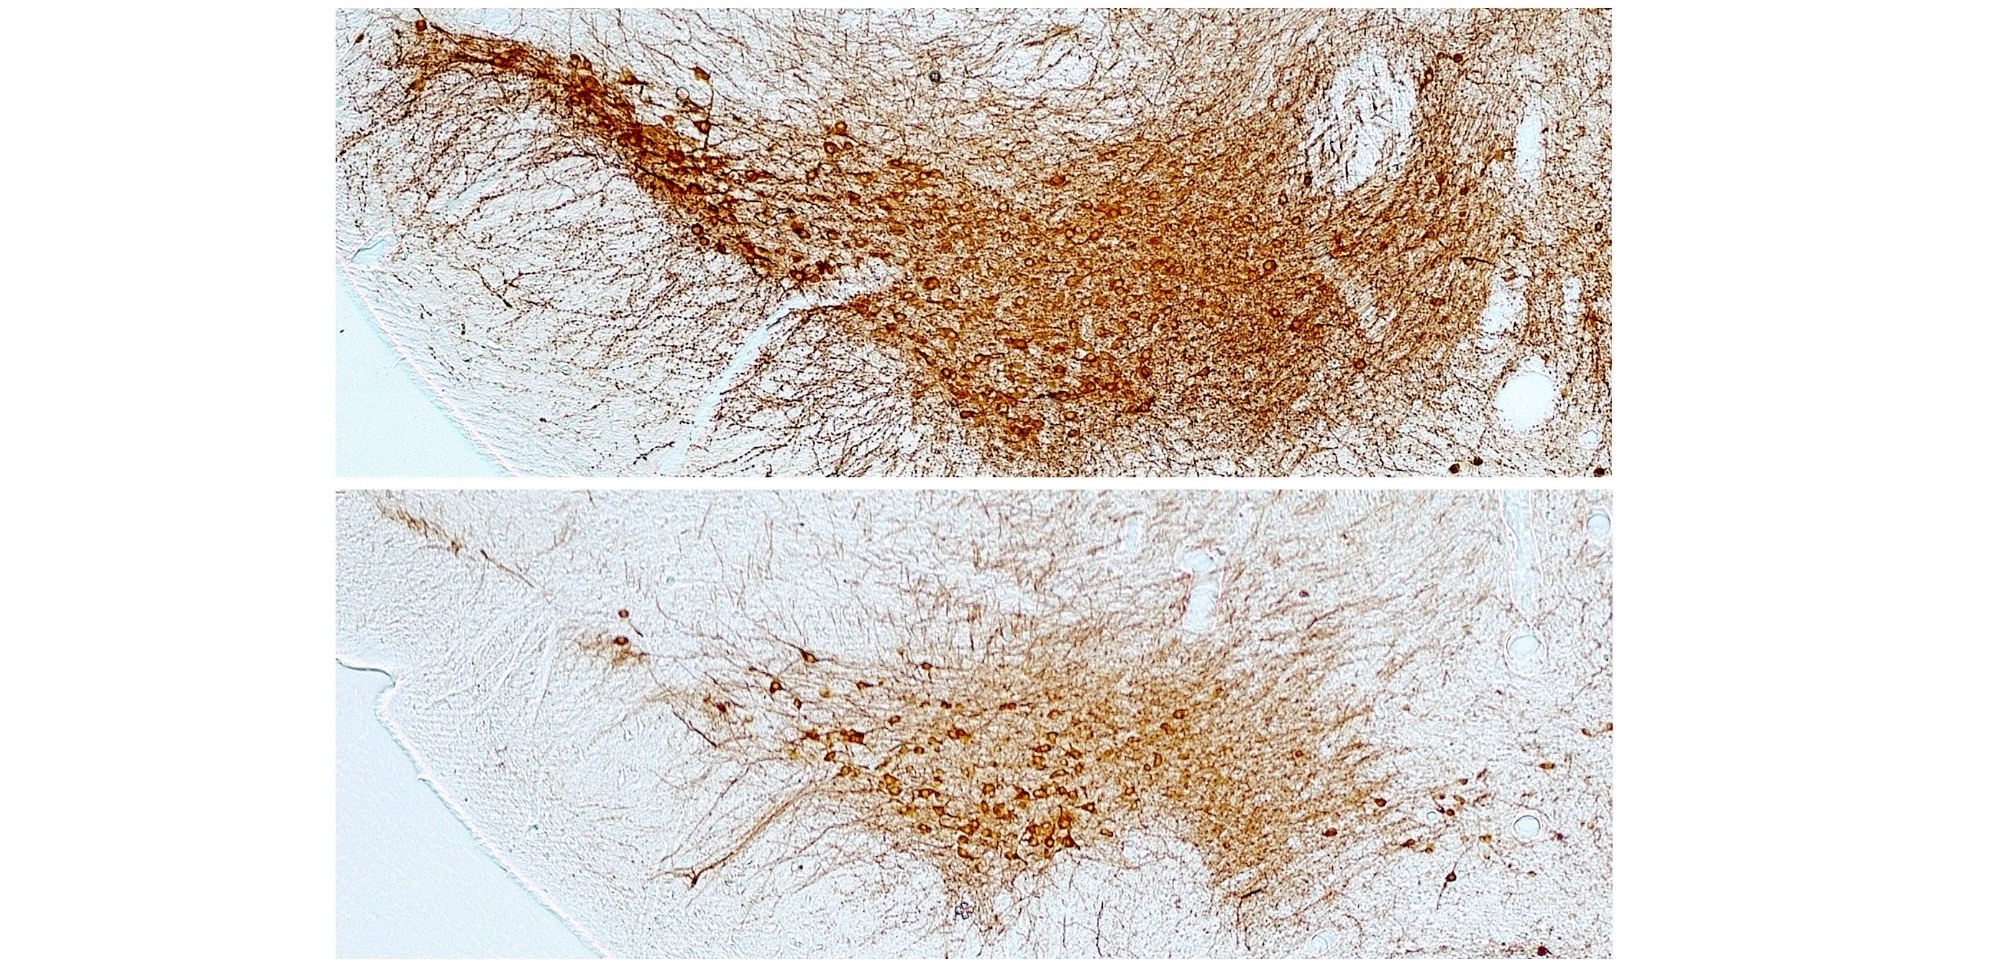

Neuronas dopaminérgicas de la sustancia negra del cerebro tras la administración de una dosis baja de la neurotoxina 6-hidroxidopamina. Arriba, ratón sano, abajo ratón diabético en el que se aprecia la pérdida de neuronas. / Mario Vallejo y Iara Pérez-Taboada

Las neuronas afectadas tienen su somas o cuerpos celulares en una zona del cerebro denominada sustancia negra y proyectan sus prolongaciones o axones al núcleo estriado, una región del cerebro encargada de la función motora y el movimiento del cuerpo.

Además, los investigadores observaron que, aunque los efectos de la diabetes no son suficientes para inducir alteraciones motoras, sí que aumentan la vulnerabilidad de las neuronas dopaminérgicas haciéndolas más sensibles a degenerar por un estímulo nocivo y dar lugar a la aparición de síntomas motores. Curiosamente, estos efectos parecen estar asociados a la hiperglucemia o a la ausencia de señalización por insulina, pero no a la existencia de obesidad, ligada normalmente a la diabetes tipo II, el tipo más frecuente en humanos.